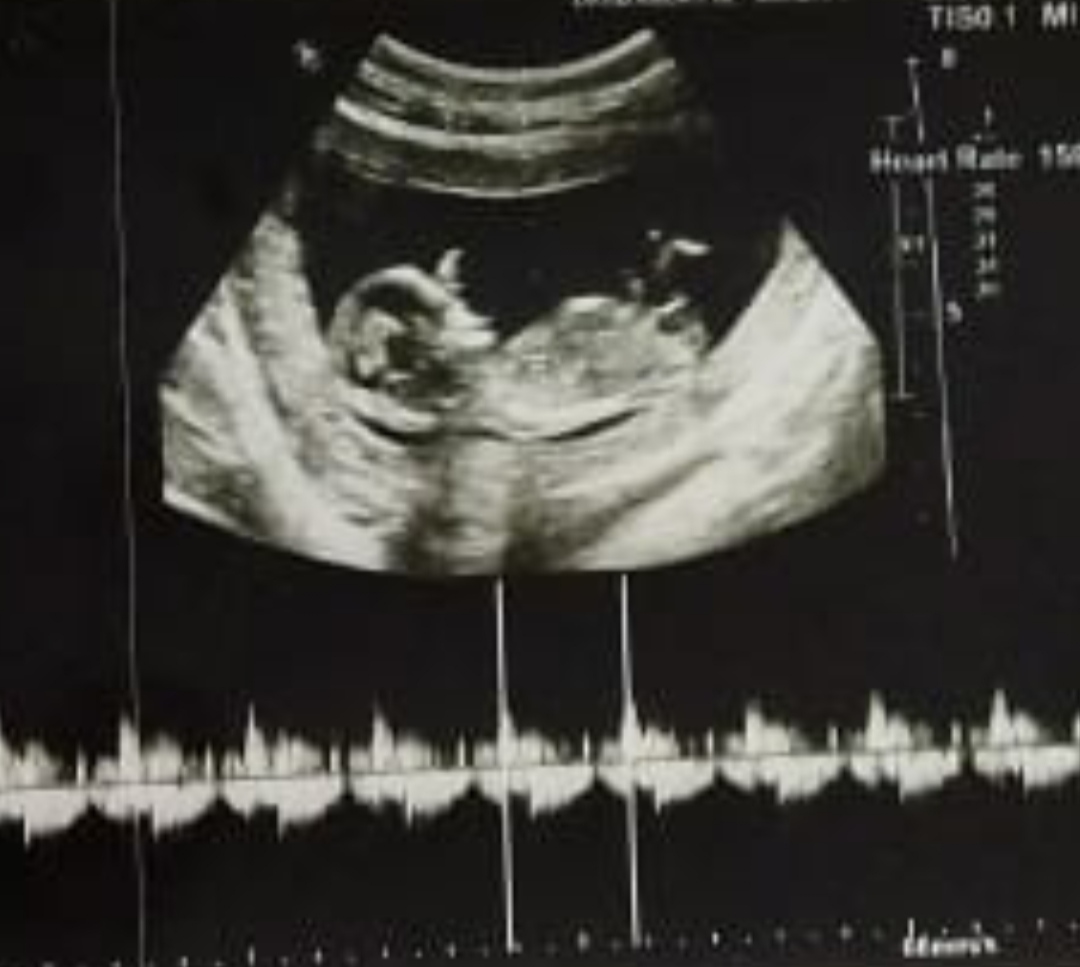

هفته ۳۲ بارداری

حرکات جنین بیشتر روی ناف هس. و وقتی خودشو میکشه بالا .مثلا سمت چپ ناف یهو میاد بالا در حد دوسه انگشت بالاتراز ناف. خیلی نگرانم. حرکاتش نباید بالاتر باشه؟